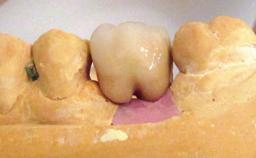

| Prosthesis Type | FDP |